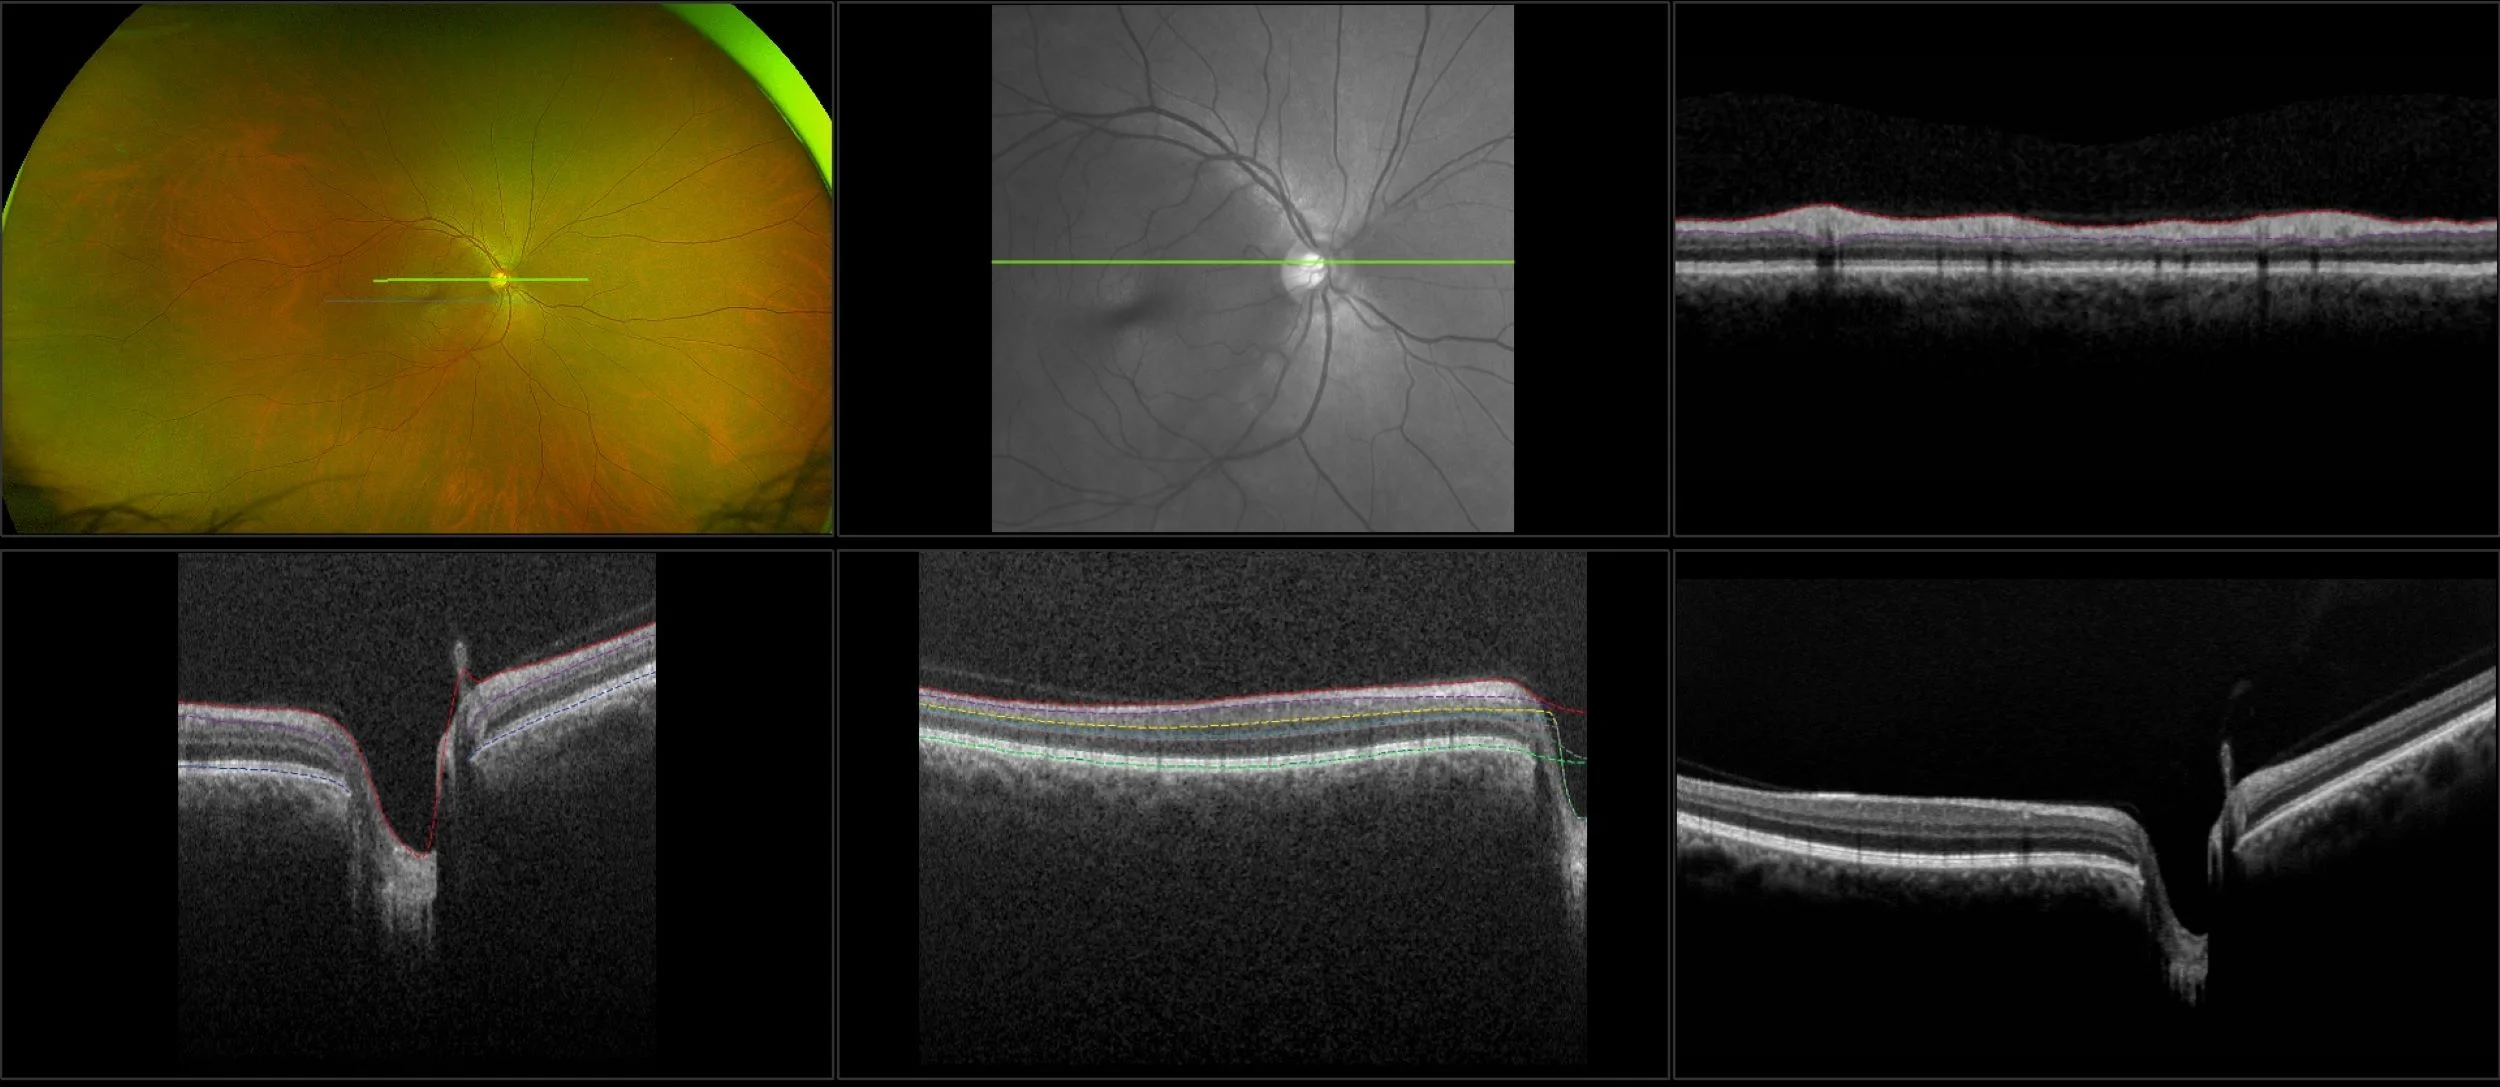

Glaucoma is a group of eye diseases that progress gradually, stealing sight, without showing symptoms. The word ‘glaucoma’ is actually an umbrella term for a group of eye diseases that damage the delicate fibers of the optic nerve. Damage is often the result of high fluid pressure inside the eye. Glaucoma can affect people of all ages but is most prevalent in middle-aged adults and the elderly. Results from published clinical studies suggest that optomap may play an essential role in glaucoma management. Optos devices capture and provide details needed for glaucoma exams such as segmentation and reference data specifically found with the MonacoPro device, while simultaneously delivering an integrated view to the eye.